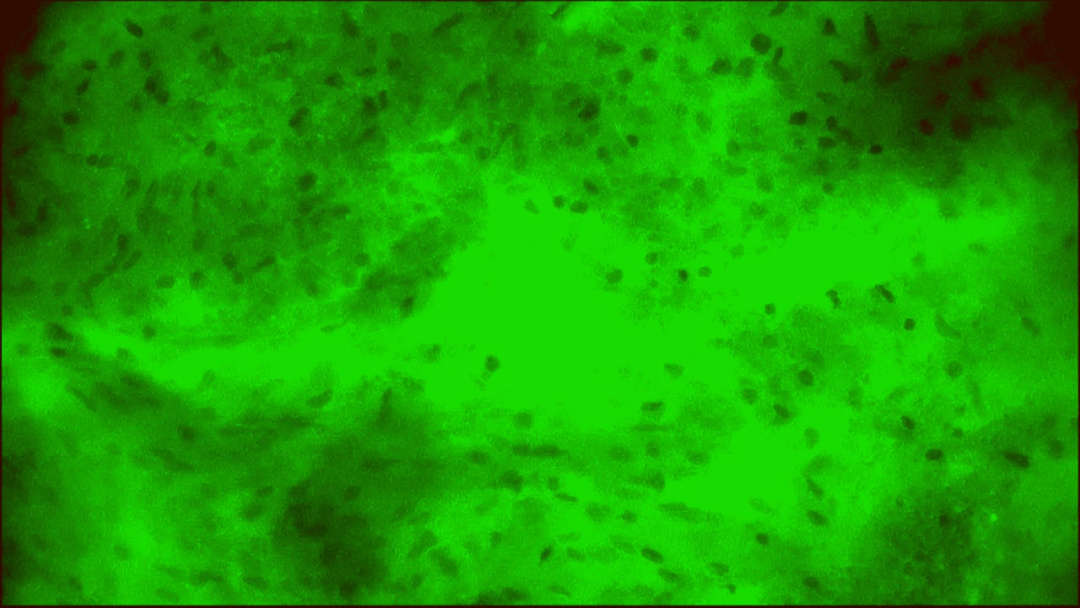

術中EndoSCell?細胞圖像如下:

腫瘤核心區(qū)域:細胞核異型性顯著,分布密集且不規(guī)則,陽性。

腫瘤殘腔切緣:細胞核異型性顯著,分布密集且不規(guī)則,陽性。

擴切后的正常細胞組織:細胞核形態(tài)正常,分布均勻,陰性。